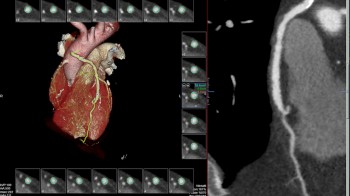

Također u slučaju pojave boli u prsima, gdje nema EKG promjena i lab.nalazi su uredni, radi se takozvani «triple rule-out» CT koronarografija-da bi se jednim pregledom isključila bolest koronarnih arterija, plućna tromboembolija ili disekcija aneurizme aorte, od kojih je svaka ponaosob potencijalno fatalna.

• MSCT koronarografija (prikaz krvnih žila srca CT-om, bez neugodnosti i komplikacija koje nosi klasična koronarografija), u saradnji s Poliklinkom dr.Al-Tawil